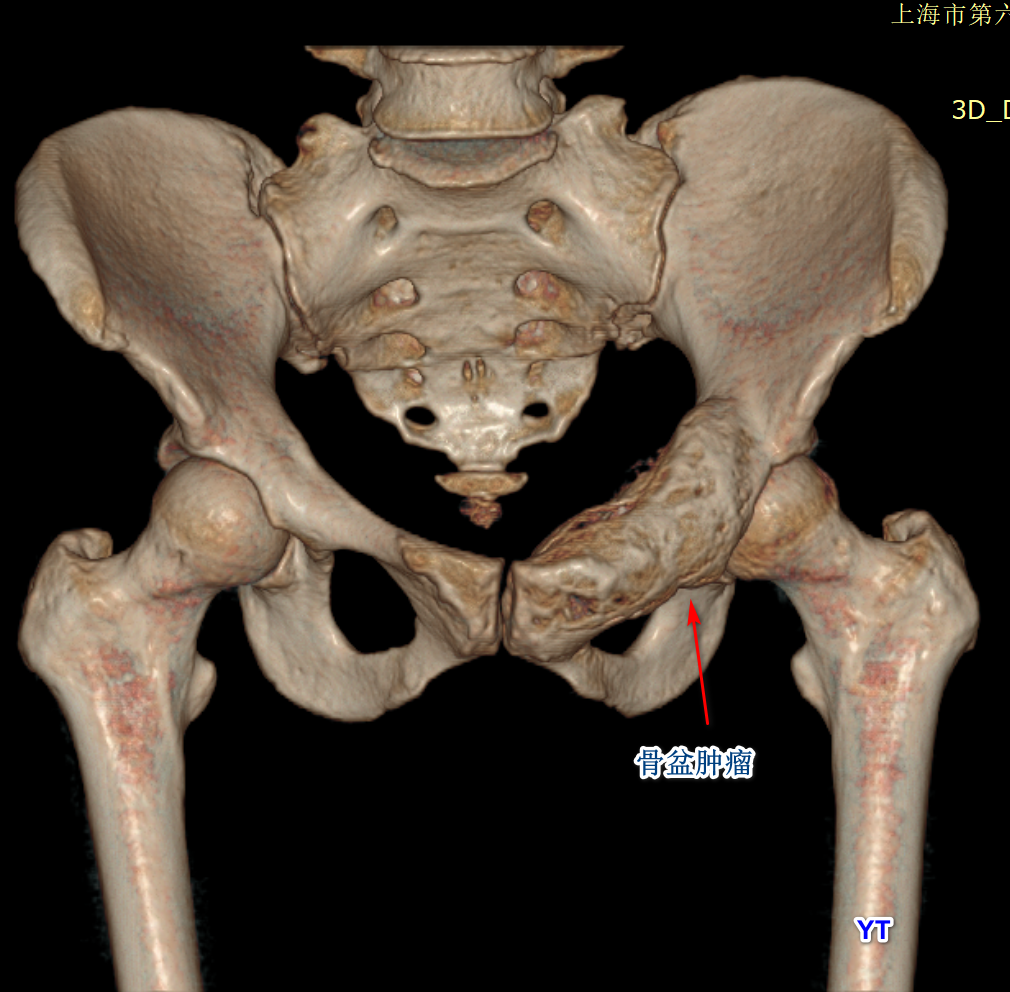

袁霆,國家骨科醫(yī)學(xué)中心主任醫(yī)師,上海六院骨科骨腫瘤科主任醫(yī)師,上海交通大學(xué)研究生導(dǎo)師一、骨盆腫瘤:隱藏在人體“核心區(qū)”的致命威脅骨盆是人體承上啟下的“核心區(qū)”,包裹著腸道、膀胱、子宮、血管和神經(jīng)等關(guān)鍵器官。然而,這個(gè)復(fù)雜的解剖結(jié)構(gòu)也讓它成為骨腫瘤的“高危地帶”。骨盆惡性腫瘤早期癥狀隱匿,患者常因輕微疼痛或排尿困難誤以為是痔瘡或關(guān)節(jié)炎,導(dǎo)致確診時(shí)腫瘤已長到拳頭大小,甚至壓迫器官,危及生命。更殘酷的是,傳統(tǒng)手術(shù)常需切除半側(cè)骨盆,患者術(shù)后可能面臨下肢癱瘓或終身掛尿袋的困境。即便能保肢,標(biāo)準(zhǔn)化的金屬假體也難以匹配復(fù)雜骨骼結(jié)構(gòu),術(shù)后關(guān)節(jié)僵硬、假體松動等問題頻發(fā)。二、3D打印技術(shù):從“私人訂制”到“與時(shí)間賽跑”過去十年,3D打印技術(shù)為骨盆腫瘤患者帶來了曙光。醫(yī)生可通過CT掃描數(shù)據(jù),打印出與患者骨骼完全匹配的鈦合金假體,實(shí)現(xiàn)“精準(zhǔn)替換”。但這項(xiàng)技術(shù)有個(gè)致命痛點(diǎn):從設(shè)計(jì)到假體送達(dá)醫(yī)院需3-4周。對惡性程度高的腫瘤來說,等待意味著癌細(xì)胞可能擴(kuò)散,假體尺寸也不再適用。一位醫(yī)生曾感慨:“眼睜睜看著患者的腫瘤在等待中瘋長,卻無能為力。”三、組配式假體:像“拼樂高”一樣拯救生命2021年,北京大學(xué)人民醫(yī)院郭衛(wèi)教授團(tuán)隊(duì)的一項(xiàng)發(fā)明改寫了游戲規(guī)則——3D打印鈦合金組配式人工半骨盆假體(GPS系統(tǒng))。這套假體由多個(gè)模塊組成,醫(yī)生可像“拼樂高”一樣,在術(shù)中根據(jù)實(shí)際切除范圍快速組裝,徹底告別漫長等待。這項(xiàng)技術(shù)有多強(qiáng)?時(shí)間殺手:術(shù)前無需定制,患者確診后可直接手術(shù),將治療周期從1個(gè)月壓縮至幾天。精準(zhǔn)適配:模塊化設(shè)計(jì)能靈活匹配不同切除范圍,甚至可調(diào)整角度,避免傳統(tǒng)假體“削足適履”的尷尬。功能升級:假體表面布滿微孔,促進(jìn)自體骨長入,遠(yuǎn)期穩(wěn)定性提升50%。四、技術(shù)背后的溫度:讓患者“有尊嚴(yán)地站立”醫(yī)學(xué)進(jìn)步的終極目標(biāo),不僅是延長生命,更是守護(hù)生活的尊嚴(yán)。傳統(tǒng)截肢手術(shù)雖能保命,卻讓患者陷入身心雙重創(chuàng)傷。而3D打印組配式假體的意義在于:保命更要保功能:患者術(shù)后可站立、行走,甚至恢復(fù)運(yùn)動。降低醫(yī)療成本:國產(chǎn)假體打破進(jìn)口壟斷,價(jià)格僅為進(jìn)口產(chǎn)品的1/3。推動技術(shù)普惠:全國已有十多家醫(yī)院開展此類手術(shù),更多患者無需跨省求醫(yī)。正如一位患者家屬所說:“以前覺得能活下來就是萬幸,現(xiàn)在居然還能正常生活——這是醫(yī)學(xué)給的奇跡?!蔽?、未來展望:3D打印如何改寫癌癥治療?當(dāng)前,3D打印技術(shù)已從骨骼重建延伸到血管、軟骨甚至器官打印??茖W(xué)家正在探索“生物活性假體”——植入后能釋放抗癌藥物,或攜帶干細(xì)胞促進(jìn)組織再生。也許未來某天,癌癥治療將像更換汽車零件一樣精準(zhǔn)可控。參考文獻(xiàn)GuoW,etal.?JBoneJointSurgAm.2020;102(21):e120.(郭衛(wèi)團(tuán)隊(duì)3D打印假體臨床研究)LiC,etal.?OrthopSurg.2021;13(5):1567-1574.(骨盆腫瘤多學(xué)科治療模式)DadiaS,etal.?FrontBioengBiotechnol.2022;10:901234.(生物活性植入物研究進(jìn)展)作者心語:作為一名醫(yī)生,最欣慰的時(shí)刻莫過于看到患者重新站起來的笑容。醫(yī)學(xué)技術(shù)的每一小步,都是患者生命質(zhì)量的一大步。愿科學(xué)之光照亮更多絕望中的家庭,讓“不可能”變?yōu)椤翱赡堋薄?/p>

骨盆腫瘤是診斷和治療的難題。由于骨盆的解剖位置較深,臨床表現(xiàn)較晚,骨盆腫瘤往往較大,位于骨盆內(nèi)臟和重要的神經(jīng)血管結(jié)構(gòu)附近。骨盆腫瘤的手術(shù)治療是指各種骨科腫瘤條件。一般來說,保肢的骨盆切除術(shù),而不是半側(cè)骨盆切除術(shù),同側(cè)肢體截肢時(shí),可以考慮保留一個(gè)功能性肢體而不損害手術(shù)邊緣。骨盆切除和重建有多種選擇,選擇取決于腫瘤組織學(xué)、解剖部位和范圍。骨盆腫瘤的手術(shù)方法和重建方法的選擇需要對骨盆解剖學(xué)有充分的了解,并且要仔細(xì)檢查解剖范圍。手術(shù)計(jì)劃必須在可接受的功能結(jié)果和可接受的發(fā)病率之間取得平衡。在這篇綜述中,我們描述了不同類型的骨盆切除技術(shù),以及術(shù)前影像在確定骨盆腫瘤的解剖范圍和隨后的手術(shù)計(jì)劃中的重要作用。大約15-20% 的原發(fā)性骨腫瘤和大約5% 的原發(fā)性軟組織肉瘤發(fā)生在骨盆。骨盆腫瘤與四肢腫瘤有許多重疊的特征,包括相似的組織學(xué)光譜,雖然有關(guān)鍵的區(qū)別。與周圍骨骼的腫瘤相反,骨盆的大多數(shù)骨腫瘤是惡性的,其中軟骨肉瘤、尤文肉瘤和骨肉瘤是三種最常見的原發(fā)性骨腫瘤。在40歲以上的患者中,骨髓瘤和轉(zhuǎn)移性疾病也常見于骨盆。除了原發(fā)性骨性惡性腫瘤外,某些良性和偶爾侵襲性的腫瘤如骨巨細(xì)胞瘤、動脈瘤樣骨囊腫和脊索瘤也發(fā)生于骨盆。骨盆骨腫瘤是一個(gè)挑戰(zhàn),檢測,由于其深部位置相比,腫瘤位于外周骨骼。因此,這些腫瘤在最終診斷時(shí)通常表現(xiàn)為較大的腫瘤。較大的尺寸與骨盆復(fù)雜的軟組織和骨性解剖結(jié)構(gòu)共同創(chuàng)造了技術(shù)上具有挑戰(zhàn)性的手術(shù)場景。手術(shù)治療骨盆腫瘤,包括半切除術(shù),在技術(shù)上是艱巨的手術(shù)程序,通常是為了處理惡性和一些良性骨盆腫瘤。有時(shí),一個(gè)孤立的轉(zhuǎn)移性病灶,嚴(yán)重的創(chuàng)傷或頑固性感染可能需要這樣一個(gè)廣泛的手術(shù)。因此,潛在腫瘤的生物學(xué)行為決定了腫瘤的侵襲程度或手術(shù)切緣,以及術(shù)前輔助放療和/或化療的必要性。放射科醫(yī)生在骨盆腫瘤患者的治療中起著重要作用,因?yàn)闇?zhǔn)確評估腫瘤的解剖部位和范圍對于確定手術(shù)的可行性至關(guān)重要。只有在不影響腫瘤復(fù)發(fā)所需的足夠手術(shù)切緣的情況下,能夠維持功能性肢體的情況下,才能考慮不截肢的骨盆切除術(shù)。一般來說,在考慮保肢骨盆手術(shù)時(shí)有三個(gè)關(guān)鍵的解剖學(xué)區(qū)域需要評估: 股神經(jīng)血管束、坐骨神經(jīng)和髖臼。如果三個(gè)關(guān)鍵結(jié)構(gòu)中的兩個(gè)可以幸免,患者通常是保肢手術(shù)的候選者。如果這些因素中的兩個(gè)需要犧牲,病人最好采取截肢手術(shù)。在這篇綜述文章中,我們描述了不同類型的骨盆切除技術(shù),并闡明了術(shù)前成像在確定骨盆腫瘤的解剖位置和范圍以便手術(shù)計(jì)劃中的重要作用。骨盆腫瘤的手術(shù)治療骨盆切除術(shù)的主要目標(biāo)是使用提供最低復(fù)發(fā)風(fēng)險(xiǎn)的技術(shù)完全切除骨腫瘤。同時(shí)保留同側(cè)肢體功能結(jié)果良好是理想的,但保留肢體不應(yīng)以增加復(fù)發(fā)為代價(jià)。根據(jù)腫瘤邊緣與腫瘤及腫瘤周圍水腫或強(qiáng)化(“反應(yīng)區(qū)”)的關(guān)系,有四種類型的手術(shù)切緣: 腫瘤內(nèi)、邊緣、擴(kuò)大切除。原發(fā)性骨肉瘤需要邊緣陰性切除,最好在擴(kuò)大或根治性邊緣切除。對于較寬的切緣,正常組織的袖帶仍然存在,但袖帶的大小或腫瘤與正常組織之間必要的最小距離以減少復(fù)發(fā)是有些爭議的。根治性切除包括切除整個(gè)骨盆腔,在某些情況下,腫瘤延伸到骶骨,需要進(jìn)行部分骶骨切除以達(dá)到一個(gè)陰性切緣。保肢骨盆手術(shù)Enneking 描述了保肢骨盆切除分類方案。I 型切除包括髂翼任何部分的切除。這個(gè)區(qū)域的切除有良好的功能結(jié)果。保持骨盆環(huán)連續(xù)性的髂骨翼部分切除不需要重建。完全切除髂骨會造成骶骨和髖臼之間的不連續(xù),導(dǎo)致殘余的半髖關(guān)節(jié)向上移位,因此需要重建以防止這種并發(fā)癥。因此,放射科醫(yī)生有必要評估髂骨腫瘤與骶髂關(guān)節(jié)的接近程度。II 型切除是為了髖臼周圍骨骼病變。根據(jù)定義,髖關(guān)節(jié)參與了這個(gè)過程,因此,這些切除是最具挑戰(zhàn)性的重建。不良結(jié)果和并發(fā)癥繼發(fā)于這些切除可以是顯著的。重建通常是首選的這些情況下,并存在許多選擇涉及各種裝置和假體。沒有重建導(dǎo)致連股髖關(guān)節(jié)和假關(guān)節(jié)也是一個(gè)選擇。病變的坐骨神經(jīng)系統(tǒng)區(qū)域是治療與 III 型切除。這些切除與良好的結(jié)果,因?yàn)轶y臼是幸免的。雖然骨重建是不必要的,軟組織重建通常是為了防止通過閉孔孔對盆腔內(nèi)臟器進(jìn)行疝出。放射科醫(yī)生必須仔細(xì)評估坐骨腫瘤到恥骨聯(lián)合的距離,因?yàn)樗ㄟ^完成骨盆環(huán)和固定腹直肌腱膜來提供骨盆固有的穩(wěn)定性。根據(jù)腫瘤的部位,III 型骨盆切除的患者可能會出現(xiàn)內(nèi)收肌或腘繩肌無力。當(dāng)腫瘤跨越骨盆的一個(gè)以上區(qū)域時(shí),切除類型是合并的。例如,i/II 型切除術(shù)同時(shí)涉及髂翼和髖臼。I/II/III 型骨盆切除術(shù)是真正的半骨盆切除術(shù)。骶骨受累需要行 IV 型切除術(shù)。部分骶骨切除術(shù)適用于 S2以下的腫瘤,不需要重建。同樣,放射科醫(yī)師必須仔細(xì)評估骶骨腫瘤的外側(cè)范圍,并檢查骶髂關(guān)節(jié)。不延伸至骶骨關(guān)節(jié)的骶骨外側(cè)腫瘤可以采用部分矢狀骶骨切除術(shù)治療,而向骶骨外側(cè)腫瘤延伸至骶骨關(guān)節(jié),除了部分矢狀骶骨切除術(shù)(i 型和 IV 型聯(lián)合切除術(shù))外,還需要有限度的髂后骨盆切除術(shù)。中線骶骨腫瘤(S2段的顱側(cè)和尾側(cè))需要橫行骶骨切除術(shù)(圖7)。當(dāng)骶骨腫瘤累及更多的骶骨近端部分并向前延伸時(shí),應(yīng)行全骶骨切除術(shù)。骶骨遠(yuǎn)端部分切除很少需要重建,但對于骶骨完全切除或骶1和骶2部分切除則需要重建。此外,IV 型骨盆切除可根據(jù)骶骨受累情況進(jìn)行分類: 累及同側(cè)骶骨翼(IVa 亞型) ,累及同側(cè)骶骨孔(IVb 亞型) ,累及對側(cè)骶骨孔(IVc 亞型) ,最后累及整個(gè)骶骨(IVd 亞型)[23]。主要的脊椎骨盆切除可以根據(jù)腰骶部切除的范圍,基于 S1以上的脊柱腫瘤的解剖學(xué)范圍和同時(shí)需要半骨盆切除(橫向范圍超過骶髂關(guān)節(jié))來分類。截肢術(shù)如果腫瘤需要切除半個(gè)骨盆,則進(jìn)行半骨盆切除術(shù)。術(shù)語“半骨盆切除術(shù)”是指通過 SI 關(guān)節(jié)的截肢術(shù)。如果腫瘤能夠保留下肢的主要神經(jīng)血管結(jié)構(gòu)(股動脈、靜脈、神經(jīng)以及外髂動脈和靜脈)和功能性肢體,而又不影響將腫瘤復(fù)發(fā)風(fēng)險(xiǎn)降到最低所需的廣泛切除,則可以進(jìn)行保肢性骨盆切除術(shù)。術(shù)語“內(nèi)半骨盆切除術(shù)”是一個(gè)誤稱,因?yàn)樗且环N骨盆切除術(shù)而不是截肢術(shù)。然而,這個(gè)術(shù)語在文獻(xiàn)中通常被用來描述一個(gè)局部切除包括全部或部分半側(cè)同時(shí)保留同側(cè)下肢。隨著神經(jīng)血管重建技術(shù)的進(jìn)步,95% 的患者可以采用保肢骨盆切除術(shù)而不是半側(cè)骨盆切除術(shù)和同側(cè)肢體截肢術(shù)[24]。如果有明顯的神經(jīng)血管受累、腫瘤內(nèi)感染或預(yù)期功能預(yù)后不良,則可能需要截肢。放射科醫(yī)生必須仔細(xì)評估骨盆腫瘤與腰骶神經(jīng)叢/坐骨神經(jīng)、股神經(jīng)血管束和髖關(guān)節(jié)的接近程度。如果有兩個(gè)或兩個(gè)以上的解剖結(jié)構(gòu)需要切除,殘肢基本上是無功能的,可能需要進(jìn)行外部半髖切除術(shù)而不是保肢手術(shù)。當(dāng)半側(cè)腰椎、部分或整個(gè)骶骨以及部分下脊柱連同 LS 叢一起切除時(shí),不論是否切除髖關(guān)節(jié),都需要進(jìn)行擴(kuò)大的半側(cè)腰椎切除術(shù)。骨盆部腫瘤術(shù)前局部分期的影像學(xué)對策術(shù)前磁共振成像用于評估盆腔腫瘤的范圍,并通過確定腫瘤與鄰近神經(jīng)血管結(jié)構(gòu)的關(guān)系來計(jì)劃手術(shù)切緣。這使外科醫(yī)生可以確定是否會嘗試重建,以及是否需要其他外科附屬??频膮⑴c。手術(shù)計(jì)劃的一個(gè)重要考慮因素是能否達(dá)到陰性的手術(shù)切緣。邊緣組織的質(zhì)量(假囊相對于正常組織的袖帶)與腫瘤和未受累組織之間的距離一樣重要。骨盆切除要考慮的三個(gè)主要結(jié)構(gòu)包括 LS 神經(jīng)叢/坐骨神經(jīng)、股神經(jīng)血管束和髖關(guān)節(jié)/髖臼周圍區(qū)。正如已經(jīng)討論過的,如果這些結(jié)構(gòu)中的任何兩個(gè)必須切除以達(dá)到負(fù)的邊緣,半骨盆切除術(shù)應(yīng)該被認(rèn)為是肢體功能嚴(yán)重受損。影像學(xué)X線對所有骨腫瘤患者的調(diào)查,無論是良性或惡性,都從影像學(xué)開始。影像學(xué)的主要作用包括評價(jià)骨腫瘤角色塑造內(nèi)的基質(zhì)礦化模式(軟骨樣與骨樣) ,而不是評價(jià)其程度(最好由磁共振成像進(jìn)行)。它還可以幫助我們了解骨質(zhì)脫礦的總體程度以及病理性骨折和骨量丟失的風(fēng)險(xiǎn),這些因素可能會對重建策略產(chǎn)生影響。CT對于骨腫瘤的評估,CT X射線計(jì)算機(jī)斷層成像比軟組織腫塊更有用。三維(3D)容積提供 CT 成像可用于外科醫(yī)生規(guī)劃骨盆腫瘤切除。此外,CT 和 MRI 的融合也可以提供關(guān)于骨盆骨腫瘤的骨性和骨外或軟組織成分的有用信息。與 x 線攝影相似,CT 詳細(xì)記錄了腫瘤的位置以及是否存在骨或軟骨樣鈣化和皮質(zhì)受累。由于這個(gè)原因,在評價(jià)骨樣骨瘤、骨膜反應(yīng)、基質(zhì)礦化和髂骨等扁平骨病變時(shí),有時(shí)優(yōu)于 MRI。對比增強(qiáng) CT 檢查,尤其是 CT 血管造影,可以幫助確定血管受累,這對于計(jì)劃復(fù)雜的切除手術(shù)至關(guān)重要,但是與非增強(qiáng)的圖像相比,其優(yōu)勢很小。在許多情況下,CT 最有用的應(yīng)用是指導(dǎo)活檢。一個(gè)準(zhǔn)確和適當(dāng)?shù)亩ㄎ换顧z可以是一個(gè)整體步驟的治療計(jì)劃為許多腫瘤?;罱M織檢查應(yīng)該在所有其他初步成像完成后進(jìn)行,因?yàn)榕c活檢有關(guān)的水腫或出血可能會影響圖像。活檢軌跡的規(guī)劃應(yīng)與手術(shù)團(tuán)隊(duì)協(xié)商,避免在活檢道的股直肌和臀大肌肌肉,因?yàn)樵S多腫瘤將需要切除該軌跡作為最終外科處理的一部分[27]。最后,CT 也是評估腫瘤與盆腔臟器,尤其是腸道的關(guān)系的有效手段,尤其是大多數(shù)外科醫(yī)生可能更愿意為此目的使用 CT 而不是 MRI 。在不久的將來,3D 打印技術(shù)也可能在骨盆腫瘤切除和重建的術(shù)前規(guī)劃中發(fā)揮更重要的作用。MRI雖然 MRI 和 CT 在原發(fā)性骨腫瘤的角色塑造診斷中是等價(jià)的,但是 MRI 對于確定骨盆腫瘤的范圍是不可或缺的。MRI 在確定皮質(zhì)骨和關(guān)節(jié)受累方面相當(dāng)于 CT,在確定骨內(nèi)腫瘤長度、骨外延伸和神經(jīng)血管束受累方面優(yōu)于 CT,因此,MRI 應(yīng)用于局部分期和手術(shù)計(jì)劃。多平面 t1加權(quán)自旋回波或至少兩個(gè)平面的快速自旋回波序列是最有用的骨盆骨腫瘤的局部分期由于復(fù)雜的骨盆骨解剖。T1加權(quán)序列提供關(guān)于解剖位置和參與的髖關(guān)節(jié)以及 SI 關(guān)節(jié)的信息。應(yīng)性周圍性骨髓水腫和惡性病變的擴(kuò)展。最后,彌散加權(quán)成像(DWI) ,一種定量的,非對比度的 MRI 序列,是一個(gè)有用的武器組成部分,可以有助于骨盆腫瘤的角色塑造,作為非侵襲性的對侵襲性的和治療的反應(yīng),但是對于評估病變的解剖范圍沒有什么用處。病變的邊緣有時(shí)很難與鄰近的周圍性骨髓水腫或軸性骨骼中的致密紅骨髓反應(yīng)區(qū)(特別是年輕患者)區(qū)分開來。因此,先進(jìn)的 MRI 序列,如化學(xué)位移成像和擴(kuò)散加權(quán)成像可能是有用的。為此,通過在骨髓周圍信號異常的相位圖和相位圖上繪制感興趣區(qū)域(ROI) ,對感興趣區(qū)域進(jìn)行定量分析。在1.5 t 和3.0 t 的同相和反相圖像中,信號丟失率分別大于20% 和15% ,可用于區(qū)分非骨髓替代性信號異常(如周圍水腫的顯微脂肪區(qū))和骨髓替代性腫瘤(無顯微脂肪的良性或惡性骨腫瘤)。此外,動態(tài)增強(qiáng) MRI 也有助于區(qū)分反。除了骨盆骨腫瘤的解剖學(xué)范圍外,檢測跳躍性病變也很重要,跳躍性病變最常與骨肉瘤相關(guān)。跳躍性病變是指在同一骨內(nèi)(或在軟組織肉瘤環(huán)境中的間隔)同時(shí)出現(xiàn)的額外腫瘤病灶,在組織學(xué)上與原發(fā)腫瘤分離,跳過病變有重要的手術(shù)和預(yù)后影響。術(shù)前影像學(xué)分析結(jié)合上述討論的方式,放射科醫(yī)生必須準(zhǔn)確地描述骨盆骨腫瘤的解剖位置和范圍,特別是累及 LS 神經(jīng)叢/坐骨神經(jīng)、股神經(jīng)血管束和髖關(guān)節(jié)的情況,以便手術(shù)團(tuán)隊(duì)制定切除計(jì)劃。至關(guān)重要的是,病人接受后續(xù)成像任何新輔助治療手術(shù)前,重新界定的范圍和評估治療反應(yīng)。為了評估神經(jīng)血管包裹或基臺,軸面通常是最有用的,因?yàn)樗軌蛟u估神經(jīng)血管束周圍的脂肪。雖然目前還沒有關(guān)于 MRI 區(qū)分基牙與神經(jīng)血管束包裹的準(zhǔn)確性的數(shù)據(jù),但在我們的實(shí)踐中,我們傾向于使用神經(jīng)血管束周圍脂肪的部分或完全模糊和受影響神經(jīng)內(nèi)部強(qiáng)化的神經(jīng)內(nèi)部結(jié)構(gòu)變形,以及骨骼肌去神經(jīng)支配作為神經(jīng)受累的指標(biāo)。此外,髖關(guān)節(jié)受累是至關(guān)重要的,因?yàn)樗枰P(guān)節(jié)外切除。關(guān)節(jié)內(nèi)腫塊的存在或關(guān)節(jié)內(nèi)脂肪的模糊和病理性骨折可作為關(guān)節(jié)污染的標(biāo)志物坐骨神經(jīng):通過骨盆的軸向解剖(中間加權(quán)或T1加權(quán)序列,無脂肪抑制)和流體敏感序列(T2加權(quán)脂肪抑制(FS)或短τ反轉(zhuǎn)恢復(fù)(STIR)序列)的結(jié)合,實(shí)現(xiàn)了最小二乘神經(jīng)叢和坐骨神經(jīng)路徑的最佳可視化。正常、健康的神經(jīng)在解剖圖像上與骨骼肌呈等信號,在T2加權(quán)脂肪抑制上與骨骼肌呈等信號或稍高信號,在靜脈注射造影劑后不增強(qiáng)。用于檢測神經(jīng)叢/坐骨神經(jīng)惡性病變的有用影像學(xué)特征包括神經(jīng)周圍脂肪間隙消失、周圍包裹、結(jié)節(jié)狀或球狀增大,在T2加權(quán)脂肪抑制信號升高、結(jié)構(gòu)扭曲和對比劑給藥后內(nèi)部增強(qiáng)。它也有助于尋找骨骼肌失神經(jīng)的跡象,如水腫樣信號、脂肪替代和神經(jīng)受累區(qū)域遠(yuǎn)端的神經(jīng)支配肌肉萎縮。在腫瘤涉及骶骨、髖臼后部、骨盆邊緣和坐骨大孔的情況下,應(yīng)特別注意腰骶叢和坐骨神經(jīng)。如果腰骶骨軀干能幸免,首選保肢手術(shù)。STIR序列:(核磁共振檢查序列中,有個(gè)stir序列,是一個(gè)特殊的序列,又叫脂肪抑制序列。脂肪或者病灶中存在脂肪成分在核磁共振上t1表現(xiàn)為高信號,因?yàn)榇蟛糠值牟≡钤趖1都是低信號,所以可以通過t1高信號初步判斷病灶性質(zhì)。這個(gè)時(shí)候可以加做一個(gè)stir序列,在這個(gè)序列上出現(xiàn)高信號說明是脂肪或者是含有脂肪的病灶,對診斷有決定性的意義。)股神經(jīng)血管束股動脈特征性地位于前上髂嵴之間髂腰肌肌腱交界處是髂腰肌和恥骨結(jié)節(jié)之間唯一的結(jié)構(gòu)血管和髖關(guān)節(jié)囊,因此,髖臼周圍腫瘤累及髖關(guān)節(jié)應(yīng)該仔細(xì)評估股神經(jīng)血管受累神經(jīng)最好使用核磁共振檢查,最好在軸面信號強(qiáng)度,神經(jīng)結(jié)構(gòu),以及增強(qiáng)股神經(jīng)可提示神經(jīng)受累。骨骼肌失神經(jīng)支配的跡象髂腰肌內(nèi)的骨盆受累于股神經(jīng)。任何軟組織病變涉及髂骨需要特別注意股骨神經(jīng)。骨盆病變血管受累的詳細(xì)特征至關(guān)重要,因?yàn)檠苤亟ǖ娘@著進(jìn)展允許更頻繁的肢體挽救手術(shù)干預(yù)。這最好用核磁共振來完成。據(jù)報(bào)道,彩色雙功能超聲、計(jì)算機(jī)斷層掃描和正規(guī)血管造影可用于描述軟組織肉瘤對血管系統(tǒng)的侵犯,盡管磁共振成像被認(rèn)為是金標(biāo)準(zhǔn),可以最佳地評估腫瘤血管平面的血管受累情況。正常血管周圍脂肪邊緣的缺失構(gòu)成血管受累。血管受累的分類范圍從第一類到第三類,允許臨床小組適當(dāng)?shù)赜?jì)劃其重建。ⅰ型血管受累表明動脈和靜脈均被包裹、附著或浸潤。ⅱ型病變描述的是僅影響動脈的病變,而ⅲ型病變僅影響靜脈。ⅳ型病變表明沒有血管受累,不需要血管重建。髖關(guān)節(jié)髖臼周圍骨盆腫瘤延伸至髖關(guān)節(jié)對切除和重建有巨大影響,因?yàn)轶y關(guān)節(jié)需要進(jìn)行功能性治療。在大面積骨丟失的情況下,髖關(guān)節(jié)的外科重建是非常具有挑戰(zhàn)性的,并且經(jīng)常伴隨著諸如感染和功能低下等并發(fā)癥的增加。在某些情況下,半骨盆切除可能優(yōu)于保留肢體的骨盆切除。放射科醫(yī)師必須準(zhǔn)確描述腫瘤的范圍,特別是髖關(guān)節(jié)的受累情況。髖關(guān)節(jié)解剖結(jié)構(gòu)復(fù)雜,15%的病例與相鄰的髂腰肌囊相鄰。髂腰肌囊的擴(kuò)張不應(yīng)被誤認(rèn)為是腫塊的骨外延伸。髖關(guān)節(jié)骨結(jié)構(gòu)的研究應(yīng)該從錐形和居中的x光片開始。CT是評估軟骨下板皮質(zhì)破壞的最佳方法,而MRI是評估髖關(guān)節(jié)腫瘤關(guān)節(jié)內(nèi)擴(kuò)展的首選研究。有用的影像學(xué)發(fā)現(xiàn)包括腫瘤延伸到關(guān)節(jié)腔內(nèi)的直接可視化,滑膜內(nèi)脂肪的模糊,以及髖臼周圍骨病變延伸到髖關(guān)節(jié)的病理性骨折。骶髂關(guān)節(jié)骨盆骨腫瘤可以通過骶髂關(guān)節(jié)延伸到骶骨。很少有文獻(xiàn)描述影像學(xué)在檢測骨盆腫瘤關(guān)節(jié)內(nèi)延伸至骶髂關(guān)節(jié)的準(zhǔn)確性。以組織學(xué)為金標(biāo)準(zhǔn),磁共振成像對骶骨浸潤的敏感性為100%,特異性為92%,陽性預(yù)測值為83%,骶骨浸潤被定義為骶髂關(guān)節(jié)軟骨或骨破壞或磁共振成像上存在從骨盆延伸到骶骨的異常信號。在后一項(xiàng)研究中,假陽性結(jié)果是由于瘤周反應(yīng)性水腫和紅骨髓。因此,在t1加權(quán)序列上與髂骨腫瘤相鄰的骶骨外側(cè)骨髓置換是一個(gè)有用的影像學(xué)特征。在我們的實(shí)踐中,我們使用非對比T1加權(quán)序列、化學(xué)位移成像和對比后磁共振成像序列的組合來確定硅關(guān)節(jié)的受累情況。侵犯骶髂關(guān)節(jié)需要修改手術(shù)計(jì)劃,包括更復(fù)雜的脊柱切除和重建。此外,骶骨骨髓置換相對于神經(jīng)孔的范圍有助于確定截骨部位(包括骶骨翼、骶骨中線和對側(cè)骶骨或髂骨翼)以及是否需要結(jié)扎同側(cè)或雙側(cè)骶神經(jīng)根。盆腔臟器最后,重要的是評估骨盆內(nèi)骨腫瘤的延伸和骨盆內(nèi)臟的受累,如胃腸道和泌尿生殖道,因?yàn)檫@改變了手術(shù)計(jì)劃,可能需要在確定的手術(shù)治療中有額外的手術(shù)小組在場。大的骨盆骨腫瘤與鄰近的臟器非常接近,可能需要對鄰近的器官如輸尿管、膀胱、直腸/結(jié)腸、子宮和附件進(jìn)行廣泛的整體切除,以獲得滿意的邊緣。由于總體上肉瘤的罕見性,缺乏文獻(xiàn)描述CT或MRI檢測盆腔骨腫瘤內(nèi)臟受累的準(zhǔn)確性。在臨床實(shí)踐中,CT是評估盆腔腫瘤與鄰近臟器接近程度的有效手段[29]。雖然胃腸道和胃腸道經(jīng)常移位,但它們很少被侵犯。在疑似輸尿管梗阻的情況下,可能需要進(jìn)行術(shù)前膀胱鏡檢查和輸尿管支架置入術(shù)。如果懷疑有腫瘤浸潤,膀胱鏡檢查仍然是評估下尿路的金標(biāo)準(zhǔn)。骨盆腫瘤伴有較大的軟組織腫塊,需要細(xì)致的放射制定適當(dāng)?shù)氖中g(shù)計(jì)劃。骨腫瘤和骨軟組織腫瘤的術(shù)前切除計(jì)劃需要放射科醫(yī)生的準(zhǔn)確和深思熟慮的輸入,特別注意關(guān)鍵的神經(jīng)血管和骨結(jié)構(gòu)。此外,如果現(xiàn)有的主要診斷影像學(xué)不能提供足夠的信息來正確地描繪出骨盆骨腫瘤的解剖學(xué)范圍以供手術(shù)治療,那么在手術(shù)計(jì)劃之前應(yīng)該重復(fù)進(jìn)行綜合影像學(xué)檢查。如果兩種技術(shù)的手術(shù)邊緣相當(dāng),軟組織覆蓋充分,并且可以保留功能性肢體,則肢體保留手術(shù)優(yōu)于截肢手術(shù)或外部半骨盆切除術(shù)。對于有明顯骨外擴(kuò)展和神經(jīng)血管受累的病變,半側(cè)骨盆切除術(shù)可能是首選。骨盆腫瘤的解剖學(xué)范圍是影像學(xué)研究的重要內(nèi)容,有助于指導(dǎo)臨床團(tuán)隊(duì)確定手術(shù)切緣,鑒別正常組織周圍的反應(yīng)區(qū)。